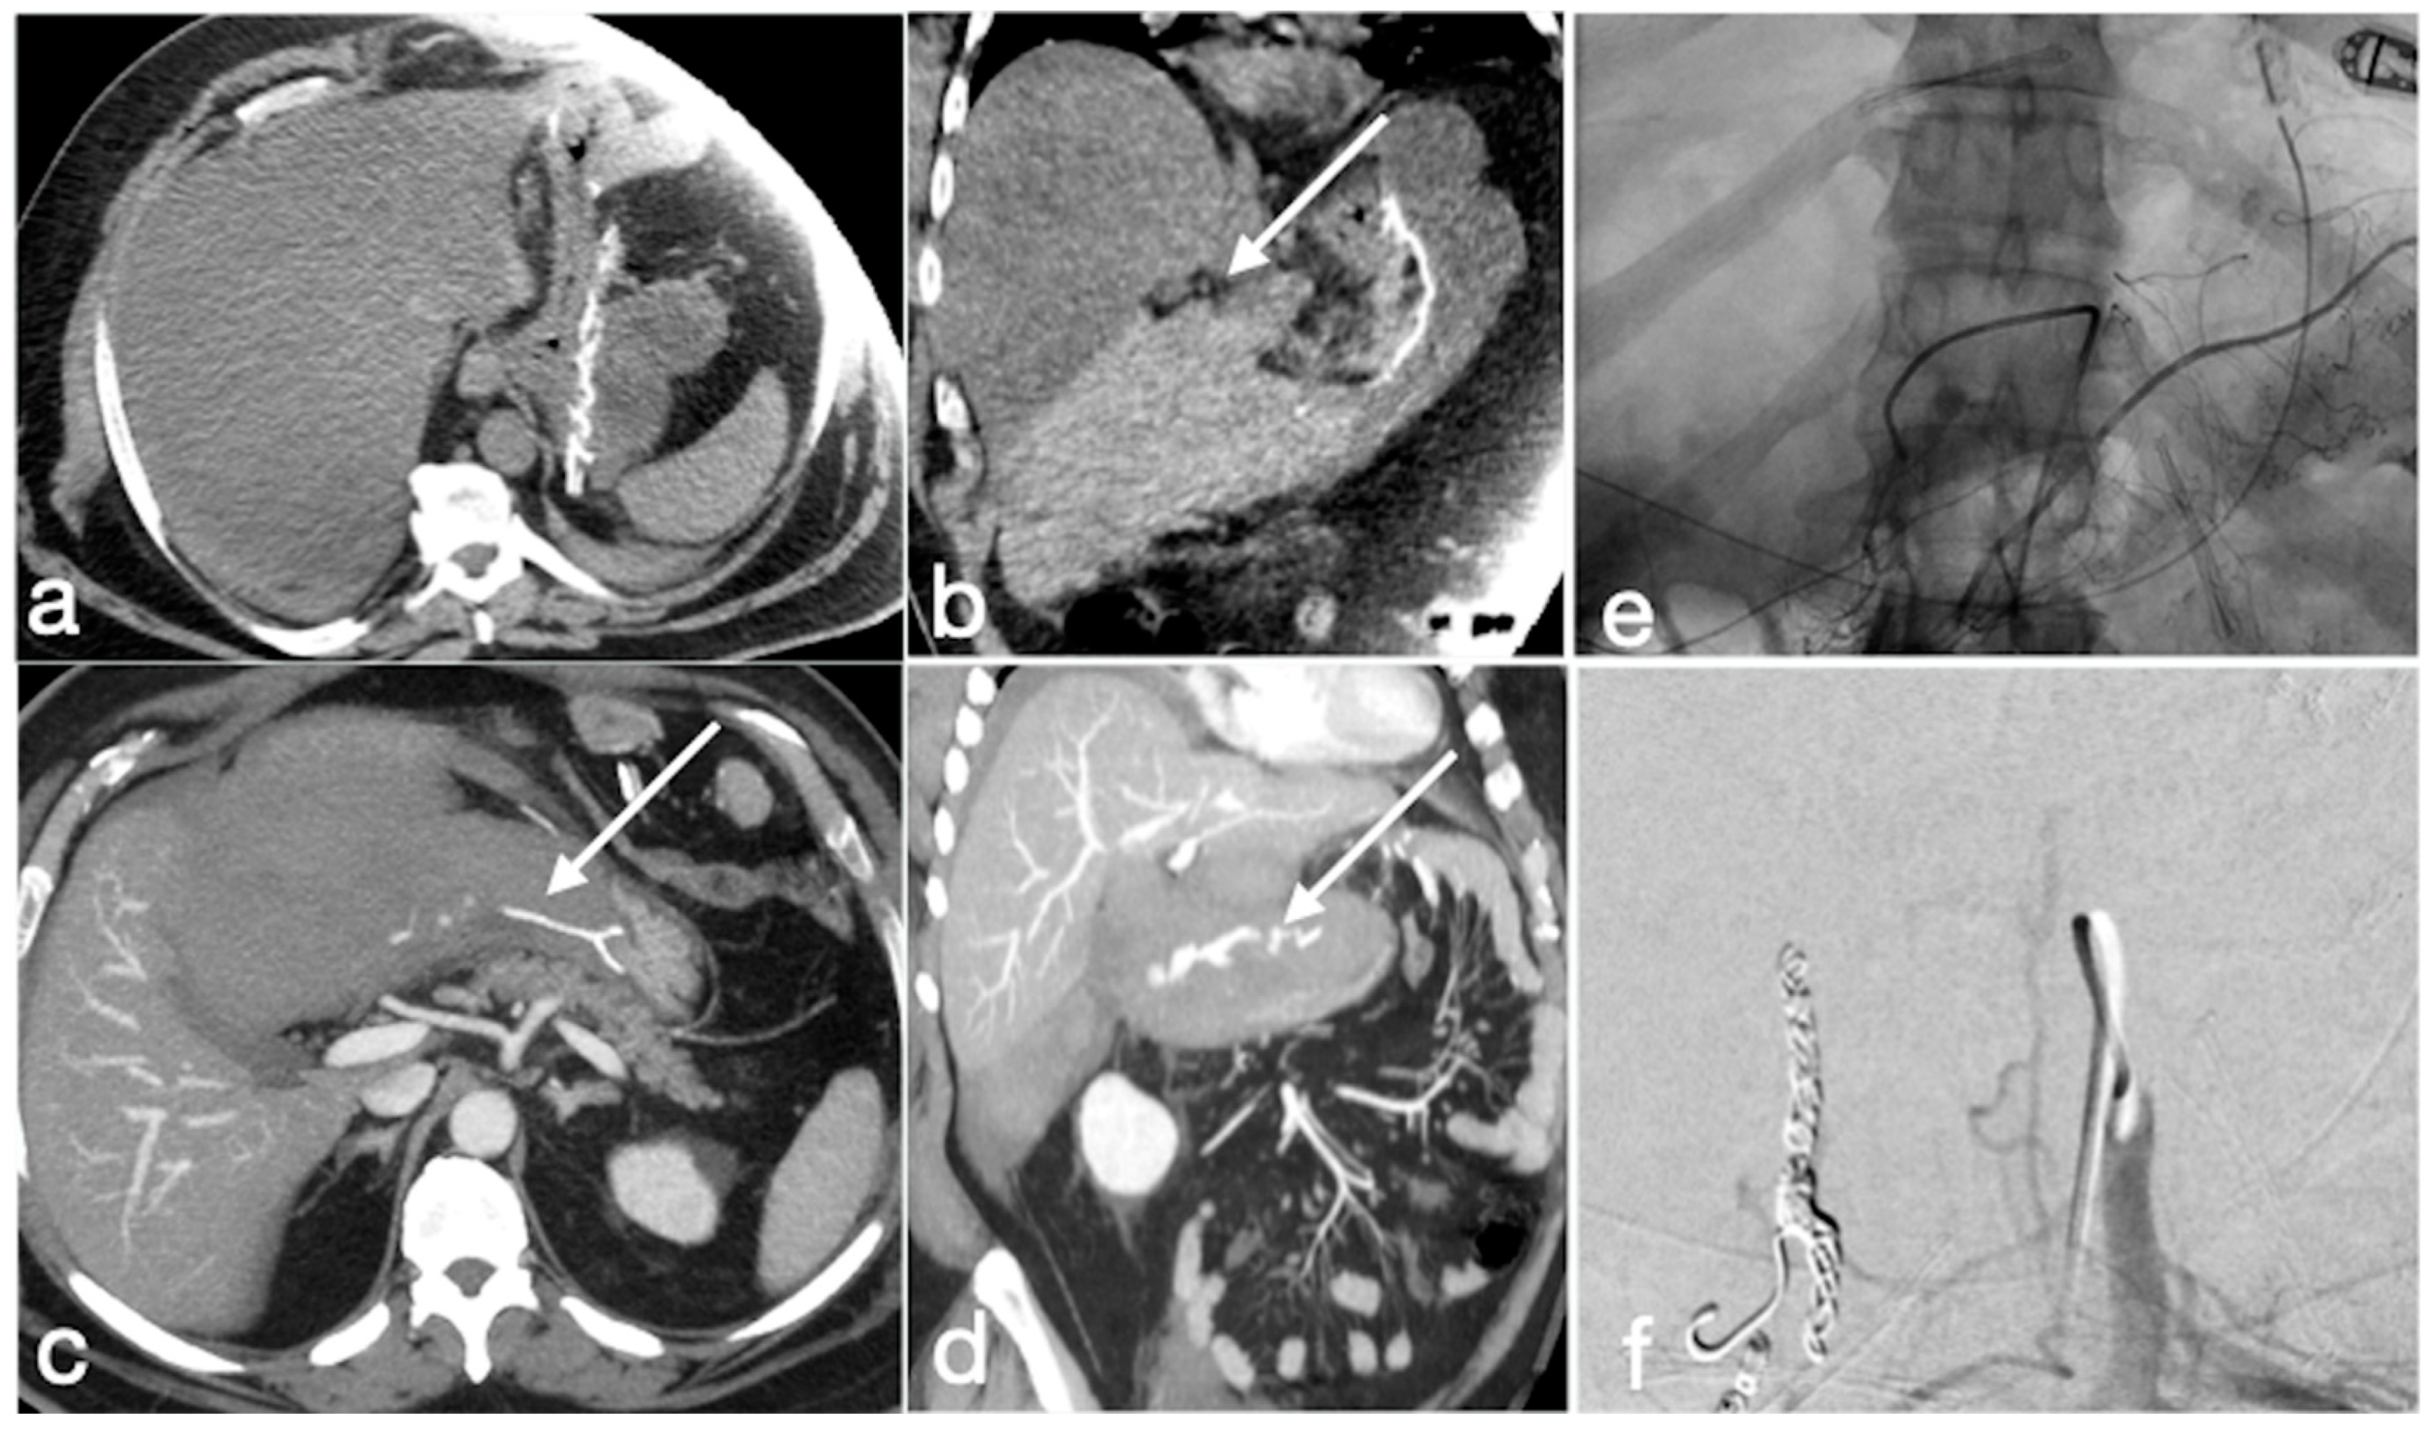

Figure 15. Spleno-portal thrombosis and liver abscesses after sleeve gastrectomy with suture leak. A 46-year-old female with a type I leak after sleeve gastrectomy complained of abdominal pain, fever and kidney failure. Note the gastric surgical suture (a, coronal oblique view), the presence of a type I leak (b, axial view, straight arrow), and of multiple liver abscesses (bd, axial view, curved arrows) related to extensive spleno-portal thrombosis (df, straight arrows). The leak is responsible for spread of gastric content and bacteria, causing septic spleno-portal thrombosis and, consequently, liver abscesses. The leak was conservatively treated and the thrombosis was successfully treated with multiple sessions of transhepatic catheter-directed thrombolysis.